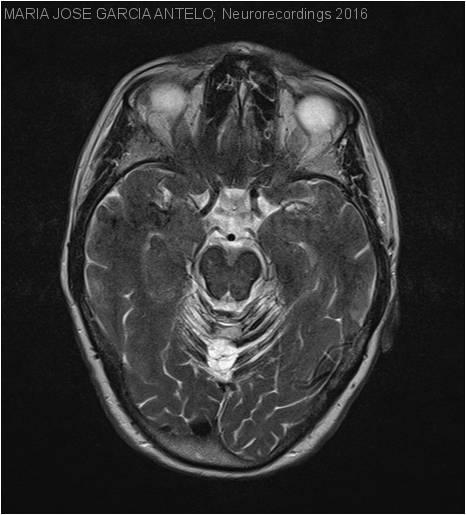

Siderosis Superficial del Sistema Nervioso Central

Diagnóstico final: Siderosis Superficial del Sistema Nervioso Central

Neurología: Patología cerebrovascular | Otros

Etiología: Malformación vascular | Metabólico